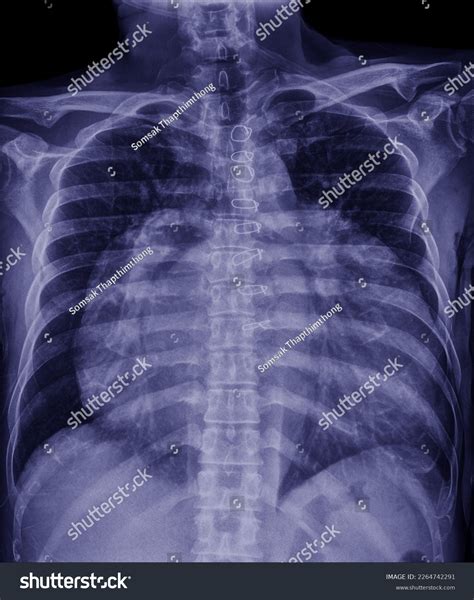

Interpreting Cardiomegaly

Airway and Bone Considerations

While the focus is often on the lungs, the X-ray also captures the ribs, spine, and the airway (trachea). Abnormalities here can include:

• Rib Fractures: Often subtle and requiring careful inspection following trauma.

• Tracheal Deviation: When the windpipe is pushed to one side, potentially by a large mass or a collapsed lung.

• Scoliosis: Curvature of the spine that can compress lung capacity.